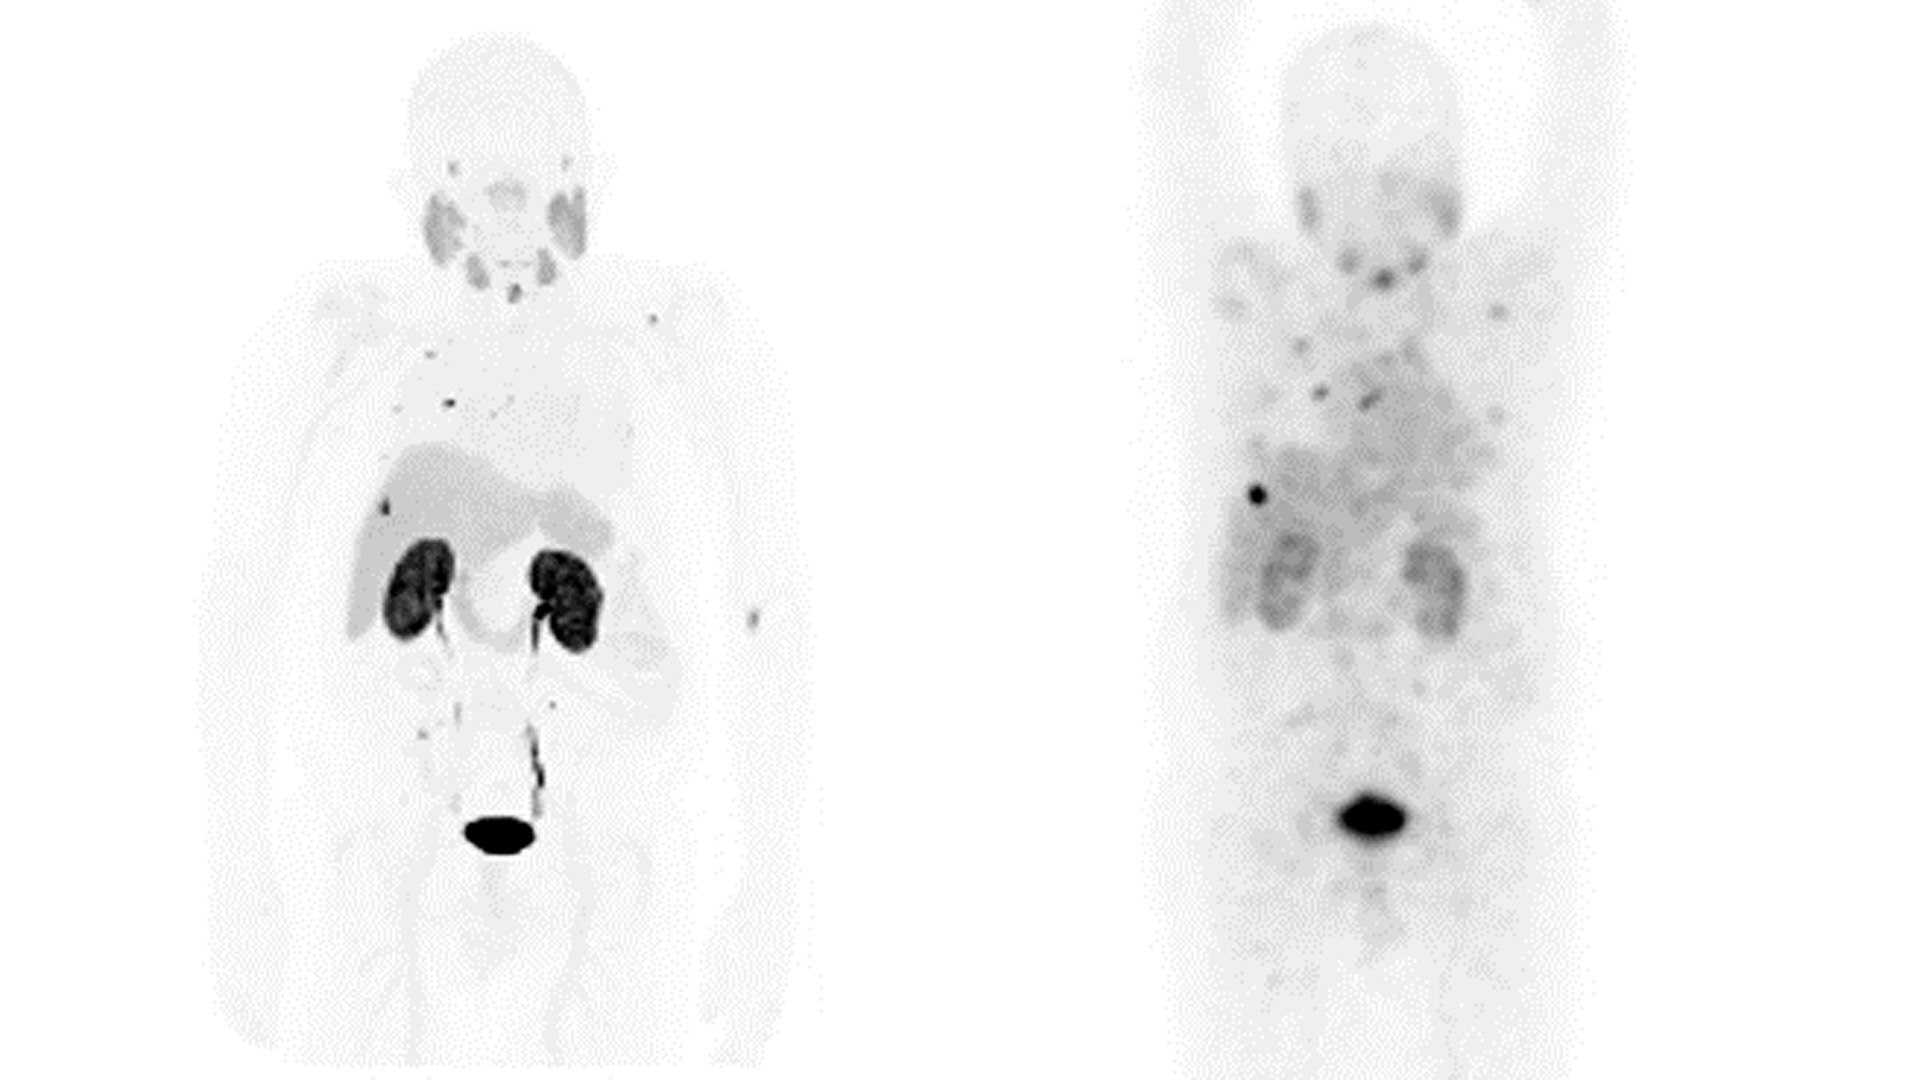

TEDAVİ GÖRÜNTÜLEME VE İZLEME

Kanser kişisel bir hastalıktır.

Tedavisi de kişisel olmalıdır.

GE HealthCare, hassas görüntüleme ve izleme çözümleri ve tedavi yanıtına yönelik inovasyonlarla bugün Teranostiğin geleceğini şekillendirmektedir.